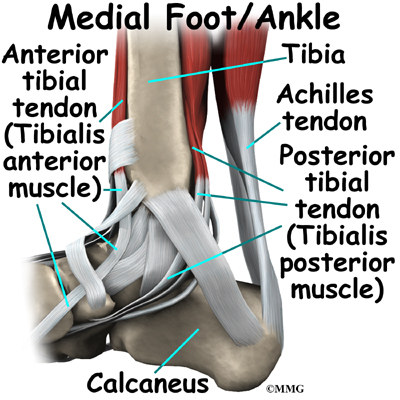

Ankle Anatomy | EOrthopod.com

eorthopod.com

eorthopod.com

ankle anatomy medial tendons muscles tendon foot joint posterior tibial ligaments malleolus anterior lateral outer calf tendonitis called where achilles